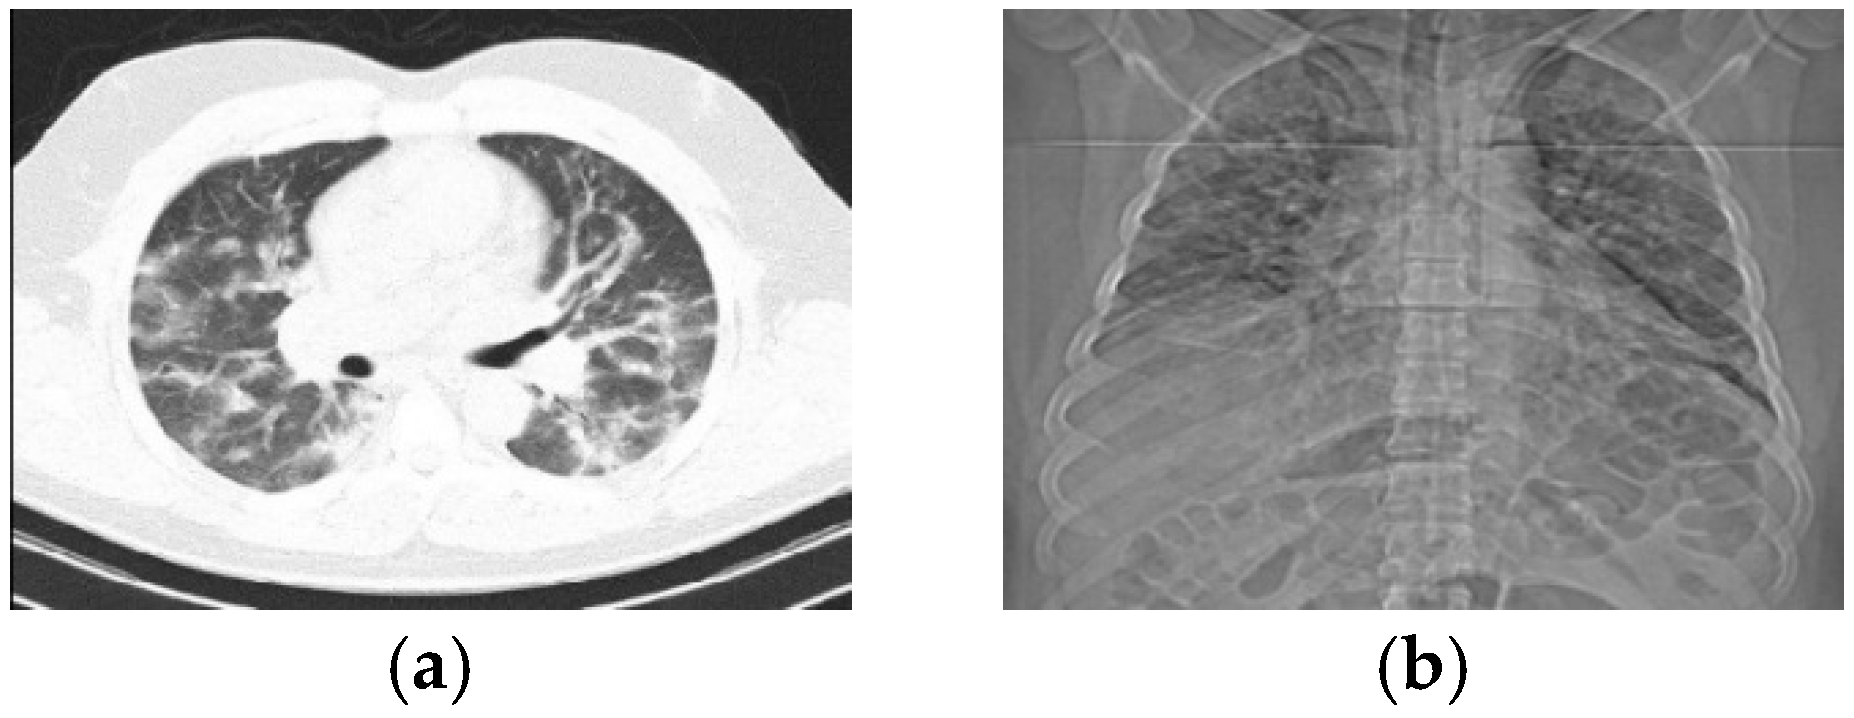

4.1. Datasets

- Zhao, J.; Zhang, Y.; He, X.; Xie, P. Covid-ct-dataset: A ct scan dataset about COVID-19. arXiv 2020, arXiv:2003.13865. [Google Scholar]

- Song, Y.; Zheng, S.; Li, L.; Zhang, X.; Zhang, X.; Huang, Z.; Chen, J.; Zhao, H.; Jie, Y.; Wang, R. Deep learning enables accurate diagnosis of novel coronavirus (COVID-19) with CT images. IEEE/ACM Trans. Comput. Biol. Bioinform. 2021, 18, 2775–2780. [Google Scholar] [CrossRef]

- COVID-19 CT Segmentation Dataset. Available online: http://medicalsegmentation.com/covid19/ (accessed on 10 October 2023).